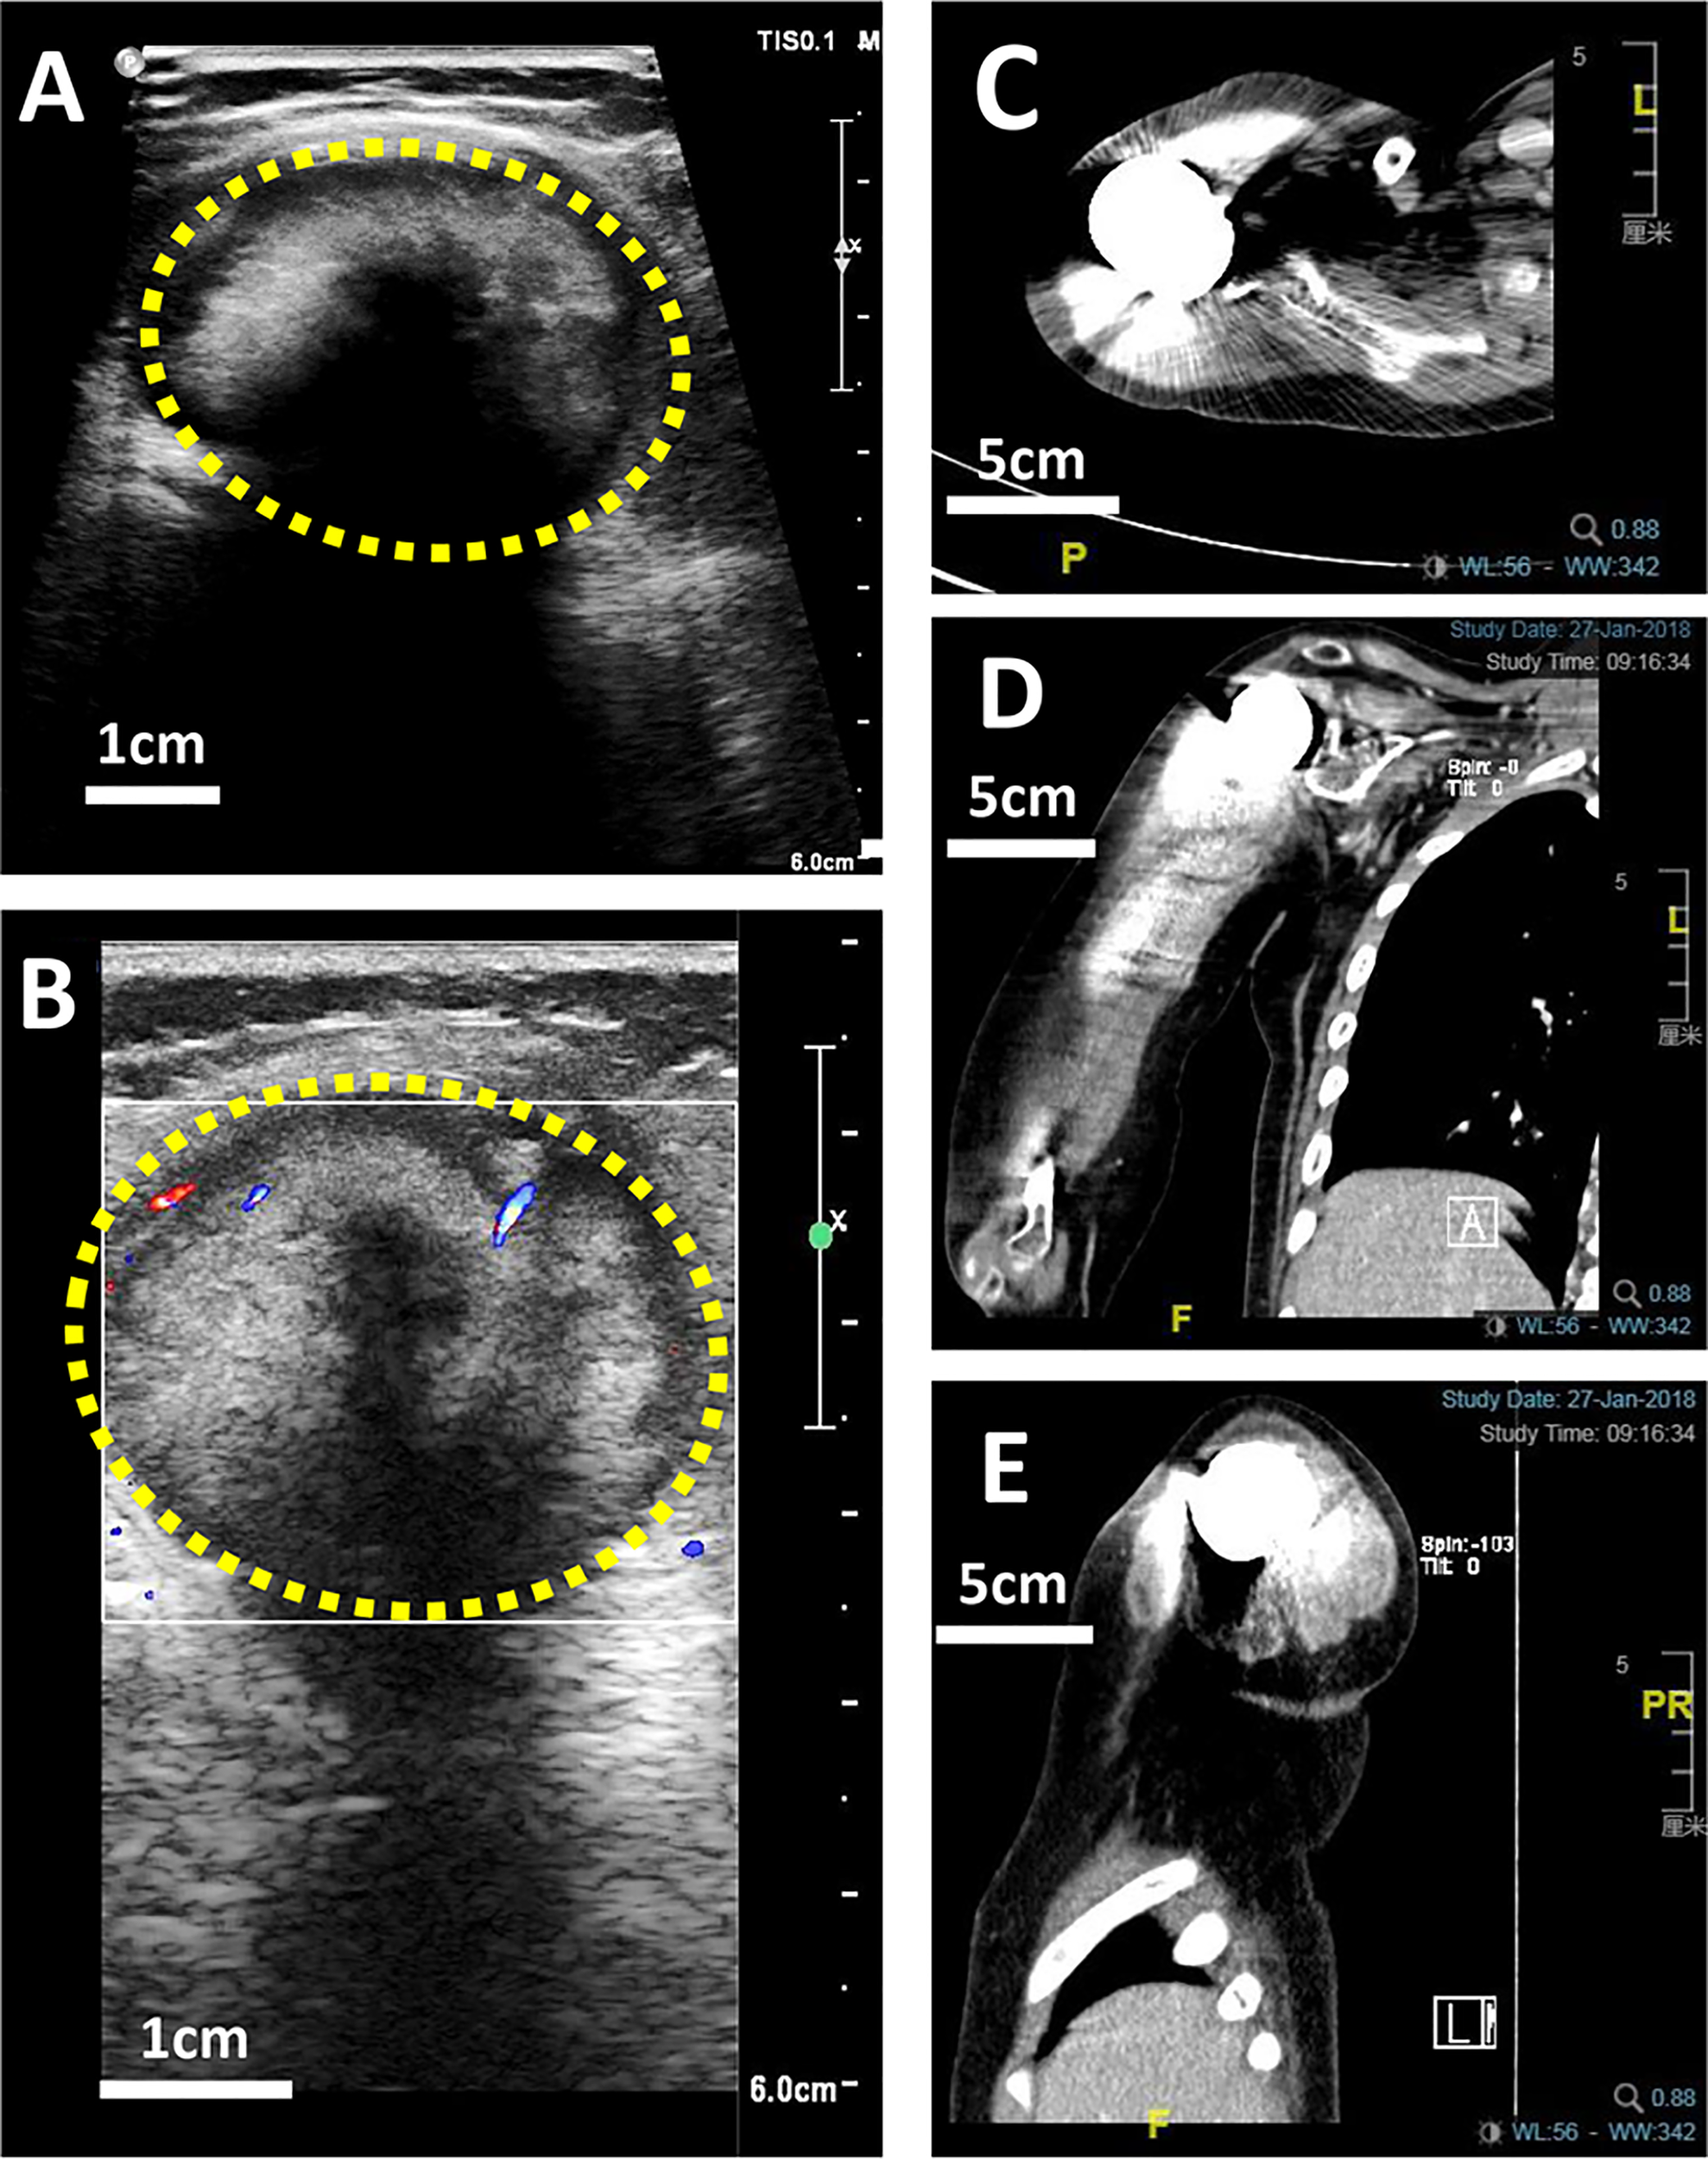

X-ray is a routine means of postoperative monitoring, which has advantages in showing abnormal changes in bone. Identifying a well-defined border is crucial for differentiating heterotopic ossification from local recurrence (20). However, it often misses minor lesions, bone marrow disease, and joint and soft tissue disease. As shown in Figure 2, it was easy to see the lesion in US but not in an x-ray image. CT has a higher spatial resolution than x-ray and can provide more information about soft tissue lesions. However, whether the benefits of using CT for early detection of lesions outweigh the risks of radiation exposure and false positives remains to be further investigated. For the cases with artificial prosthesis replacement or metal internal fixation implantation, significant artifacts are generated on CT, which affect the observation of local tissues (21, 22). As shown in Figure 3, it was easy to see the lesion in US but not in CT due to the imaging artifacts of metallic prosthesis. Systemic bone scanning with 99mTc-MDP can reveal local recurrence, systemic bone metastasis, and skipping lesions. However, the high uptake area cannot distinguish between tissue repairing response, residual disease, or recurrent lesions. A local recurrence may be found at the primary site, the stump, the resection site, or near the prosthesis. When the recurrent tumor is localized in soft tissue and does not contain sufficient mineralized osteoid, it may not be detected by conventional radiographs or even bone scans (23).

Figure 3 US and CT images of a 10-year-old boy with OS local recurrence after limb salvage with metal implants. It was easy to see the lesion in US but not in CT due to the imaging artifacts of metallic prosthesis. (A) A heterogeneous intramuscular hypoechoic mass in the right shoulder in US image. (B) Color Doppler US image of the mass. (C) The transverse plan of CT image. (D) The coronal plan of CT image. (E) The Longitudinal plan of CT image.